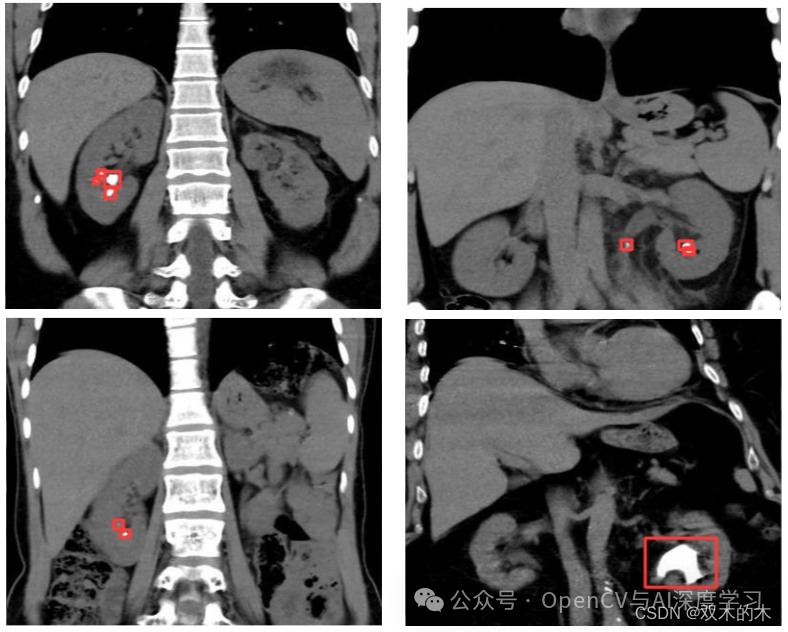

示例三:同一图像中有不同大小的肾结石(漏检+错检)

观察结果:在如上所示的样本中,我们可以观察到同一样本中存在大小和形状各异的肾结石。这对任何检测模型都构成了威胁。在这里,模型未能检测到相对较大的结石。不仅如此,模型还将白色像素伪影误认为是真正的小结石。这同样是不可接受的。